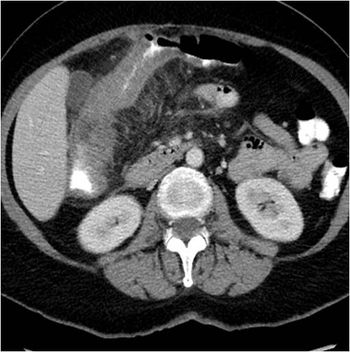

Mucinous cystadenom: 33-year-old female with abdominal distension and suspected ovarian mass. CT scan of abdomen and pelvis done with oral and intravenous contrast with multiple axial sections along with coronal and sagittal reformation.